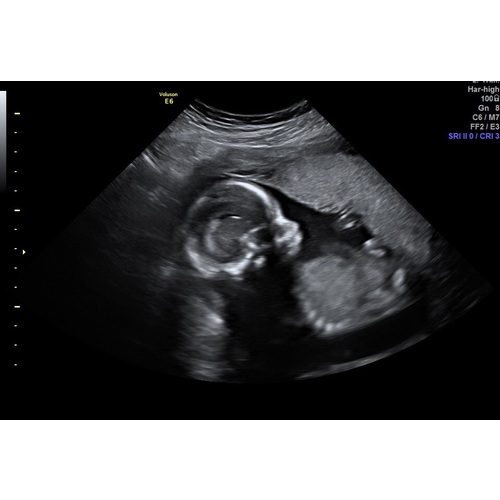

Vanmorgen ook de 20 weken echo gehad en bij ons was gelukkig ook alles goed. Was behoorlijk nerveus maar de kleine meid groeit goed en het zag er allemaal goed uit gelukkig🥰

Fijn hè om te weten dat alles goed is👍🏻 wij hebben de 20weken echo 24feb gehad en ook bij ons gelukkig alles goed. Die was onze eerste echo, twee voetjes naast elkaar 💙💙💙

26 maart een perfecte 20 weken echo gehad 🥰 ze zat zelfs boven het gemiddelde moest tussen de 350 gram en 400 gram zijn en ze was 409🥰 en ze had hele grootte voetjes bijna 36 mm 😂 al met al ik kan niet wachten om haar 23 april weer te zien!

Ik heb de echo een tijd geleden ingepland met 21 weken, zodat mijn man mee kon. Vandaag de afspraak vervroegd, want partner mag toch niet meer mee. Nu mag ik zaterdag 4 april komen, ben zo benieuwd nu ik jullie mooie foto's zie! Ik voel de baby best vaak sinds 1,5 week, dat wordt nog wat op de echo 😂

Ik heb morgen eind vd middag de 20 weken echo en mijn vriend blijft in de auto met de ipad om te videobellen. Ben mega nerveus😔 hoop zo dat alles goed is met ons kleine meisje.. Ik hou me maar vast aan het feit dat de nipt en 15 weken geslachtsbepalings echo super goed waren en goed op groei en ze al best wat konden zien aan vloeistoffen in de blaas en maag en hersenhelftjes goed verdeeld. Maar pff wat mis ik de controle bij de verloskundige om even het hartje te horen. Ook al voel ik haar elke avond kriebelen.🙈 Ben blij als morgen voorbij is en ik een beetje zekerheid heb hopelijk! 🙏